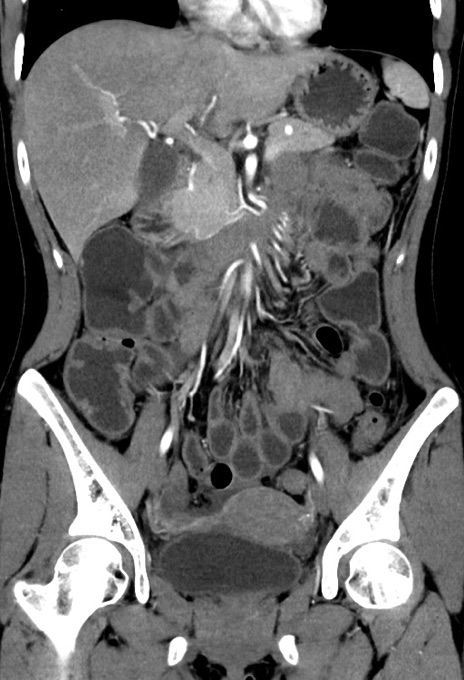

症例17(冠状断像)

【症例】20歳代女性

【主訴】嘔吐、下腹部痛

【現病歴】昨日夕食後に嘔吐し下腹部痛が出現。本日になっても嘔吐持続し改善しないため来院。

【身体所見】意識清明、BT 37.2℃、BP 108/67mmHg、腹部:平坦、やや硬、下腹部正中から右にかけて圧痛あり、反跳痛軽度あり、tapping pain(+)。

【データ】WBC 13600、CRP 14.94

横断像